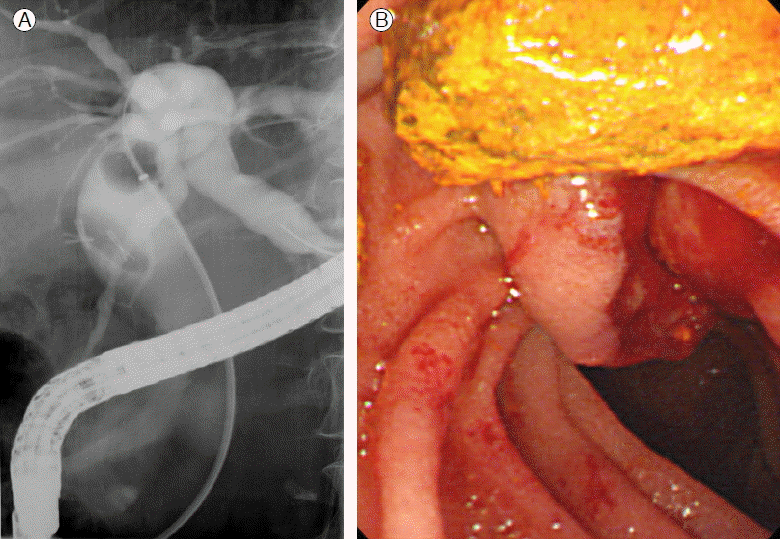

71세 여자가 개인의원에서 건강검진 목적으로 시행한 복부초음파검사에서 총담관 결석이 발견되어 입원하였다. 환자는 6년 전 급성 결석성 담낭염 진단하에 복강경담낭절제술을 시행 받았다. 입원 당시 활력징후는 정상이었고, 혈액검사에서는 AST 73 IU/L, ALT 63 IU/L, r-GT 483 IU/L, 알칼리 포스파타아제 780 IU/L이었으나, 특별한 증상을 호소하지는 않았다. 복부 X-선 검사에서 우상복부에 2개의 외과적 클립이 관찰되고 2번째 요추 우측에서 또 다른 한 개의 클립이 관찰되었고, 복부 컴퓨터단층촬영에서 경도의 총담관 확장과 총담관 내에 금속성 인공물이 관찰되었다(Fig. 1). 내시경 역행담도조영술에서 총담관의 확장이 관찰되고, 총담관 내 중심부에 외과적 클립으로 생각되는 방사선비투과 물질을 포함한 타원형의 음영결손이 관찰되었다. 내시경괄약근절개술을 시행한 후 바스켓과 회수용 풍선 카테터를 이용하여 결석을 제거하였다(Fig. 2). 제거된 결석은 갈색석이었다.

Figure 1.

Abdominal X-ray and CT scan. (A) There are two surgical clips congregated at right upper quadrant, and another one migrated distally. (B) There is high density of material in the distal common bile duct.